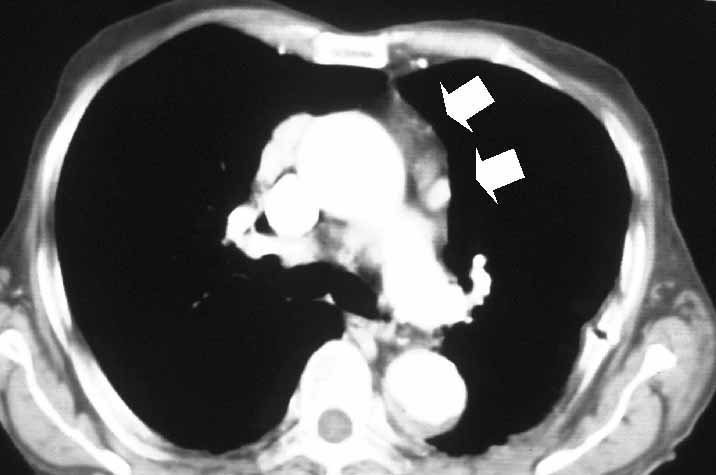

Subsequently, all mediastinal fat that is found in the pretracheal space, along the internal mammary pedicles, in the aorto-pulmonary window (Figure 7), as well as in the right (Figure 8) or left (Figure 9) pericardiophrenic angles that may contain ectopic thymic tissue is completely excised to accomplish an extended thymectomy (Figure 10).